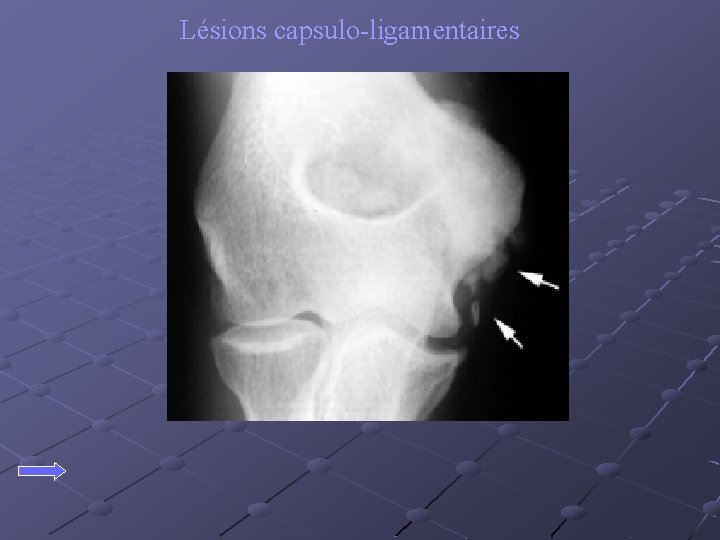

Lésions capsulo-ligamentaires